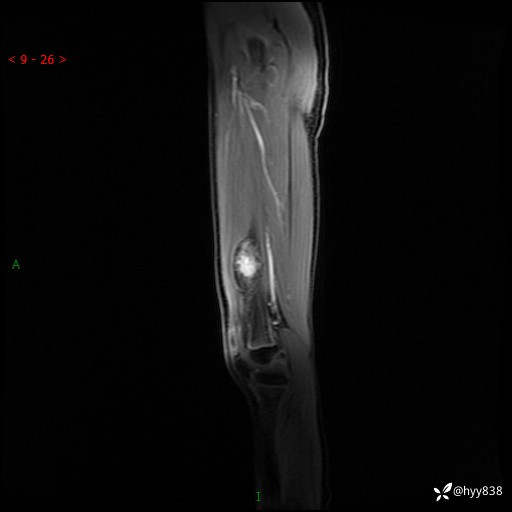

左大腿MRI平扫+增强